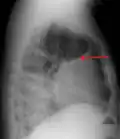

A large left-sided pleural effusion as seen on an upright chest X-ray

A pleural effusion is usually diagnosed on the basis of medical history and physical exam, and confirmed by a chest X-ray. Once accumulated fluid is more than 500 mL, there are usually detectable clinical signs, such as decreased movement of the chest on the affected side, dullness to percussion over the fluid, diminished breath sounds on the affected side, decreased vocal resonance and fremitus (though this is an inconsistent and unreliable sign), and pleural friction rub. Above the effusion, where the lung is compressed, there may be bronchial breathing sounds and egophony. A large effusion there may cause tracheal deviation away from the effusion. A systematic review (2009) published as part of the Rational Clinical Examination Series in the Journal of the American Medical Association showed that dullness to conventional percussion was most accurate for diagnosing pleural effusion (summary positive likelihood ratio, 8.7; 95% confidence interval, 2.2–33.8), while the absence of reduced tactile vocal fremitus made pleural effusion less likely (negative likelihood ratio, 0.21; 95% confidence interval, 0.12–0.37).[13]

A pleural effusion appears as an area of whiteness on a standard posteroanterior chest X-ray.[14] Normally, the space between the visceral pleura and the parietal pleura cannot be seen. A pleural effusion infiltrates the space between these layers. Because the pleural effusion has a density similar to water, it can be seen on radiographs. Since the effusion has greater density than the rest of the lung, it gravitates towards the lower portions of the pleural cavity. The pleural effusion behaves according to basic fluid dynamics, conforming to the shape of pleural space, which is determined by the lung and chest wall. If the pleural space contains both air and fluid, then an air-fluid level that is horizontal will be present, instead of conforming to the lung space.[15] Chest radiographs in the lateral decubitus position (with the patient lying on the side of the pleural effusion) are more sensitive and can detect as little as 50 mL of fluid. Between 250 and 600mL of fluid must be present before upright chest X-rays can detect a pleural effusion (e.g., blunted costophrenic angles).[16]